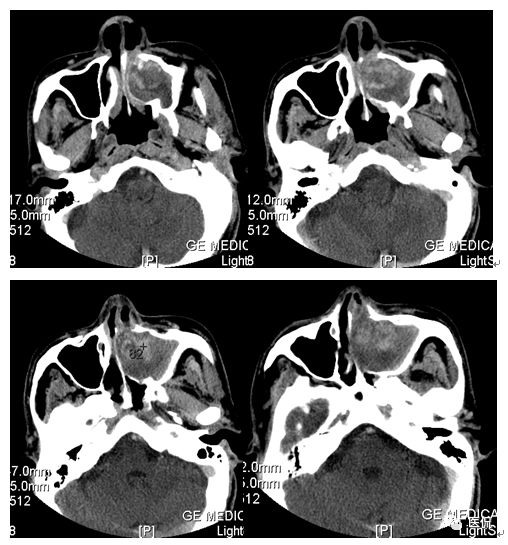

增强动脉期

增强静脉期

CT平扫及增强示:左侧上颌窦及鼻腔可见软组织密度影,呈膨胀性生长,周围骨质压迫性吸收破坏,累及左眶,病灶密度不均匀,周边区可见点状钙化,增动脉期轻度强化,局部见小灶性稍高密度区,静脉期病灶内见不均匀明显强化,CT值最高达117HU,延迟期强化范围有所增大。

本例病灶较大,周围骨质可见吸收破坏,并累及眼眶,病灶内少量钙化,增强扫描具有一定特征性,表现为动脉期轻度强化,局部见小灶性稍高密度区,静脉期病灶局部呈明显强化,CT值最高达117HU,延迟期强化范围有所增大,呈延迟渐进性强化的特点,推测为病灶内出血所致。